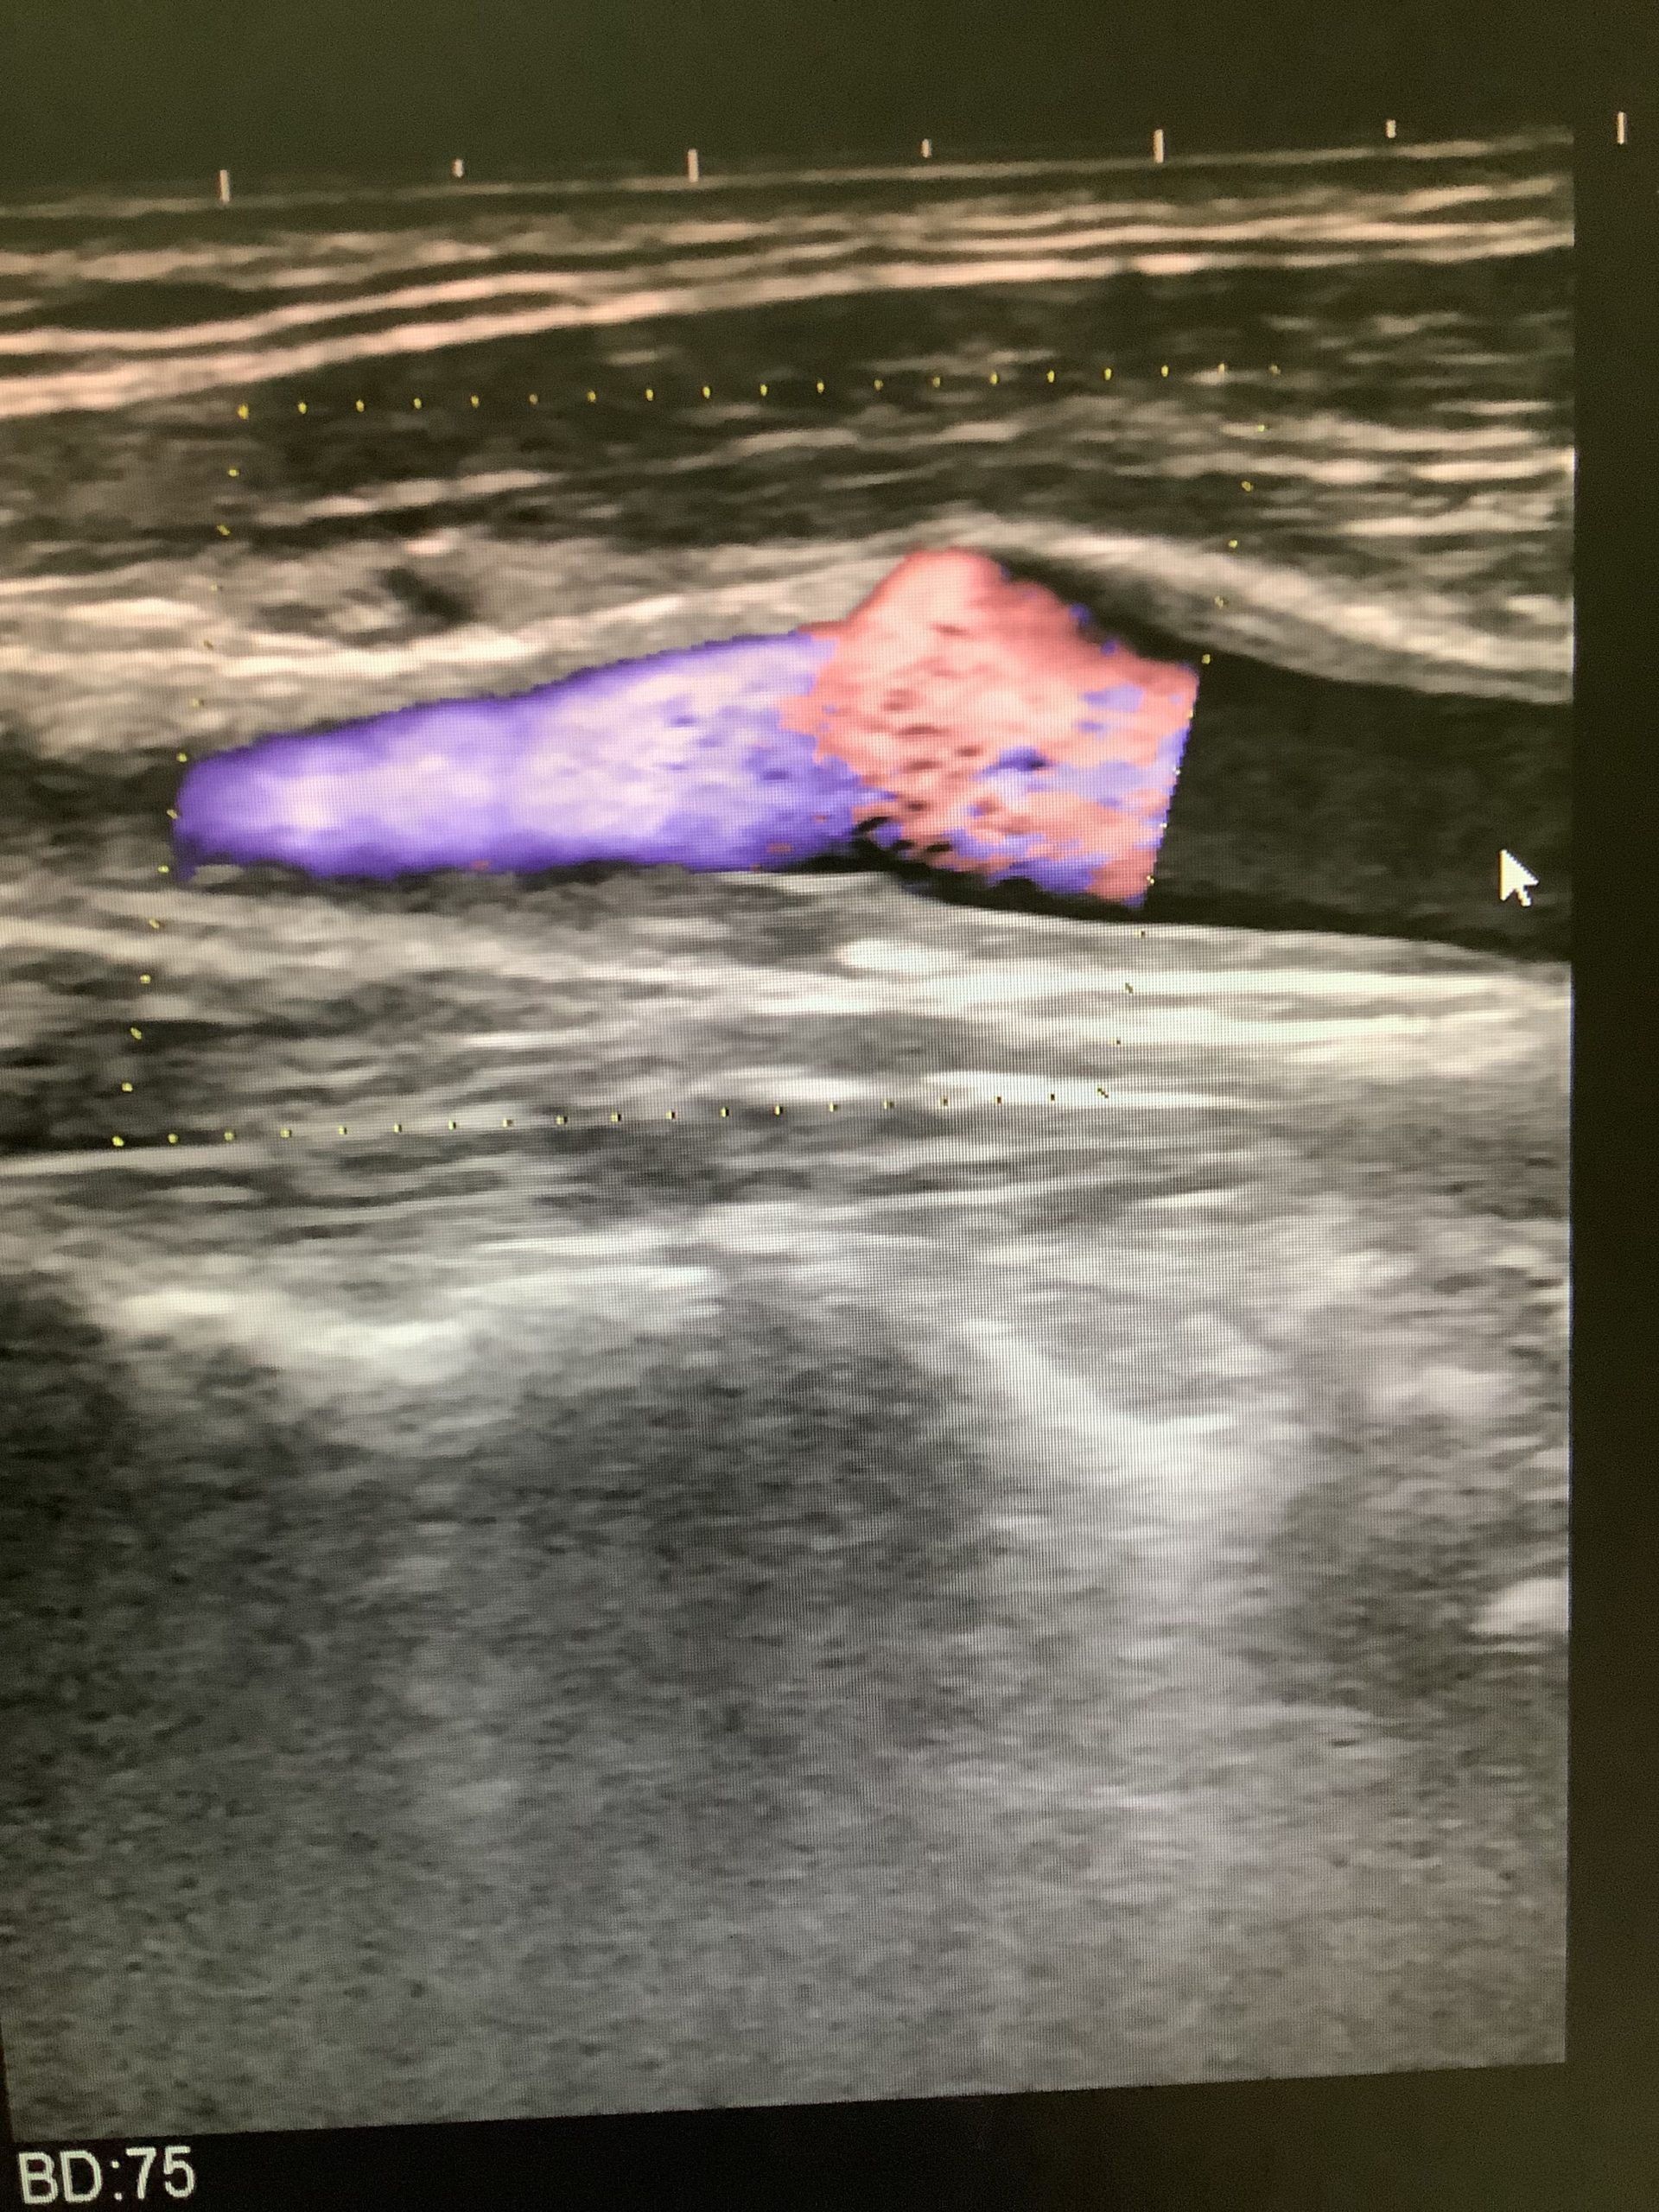

頸動脈エコー検査

今回は頸動脈エコーについてご紹介します。

頸動脈は脳に血液を送り込む血管です。

そのため、頸動脈の動脈硬化の有無、血管の詰まり具合、プラークの状態を調べることで、

心筋梗塞や脳梗塞のリスクが高いかどうかがわかります。